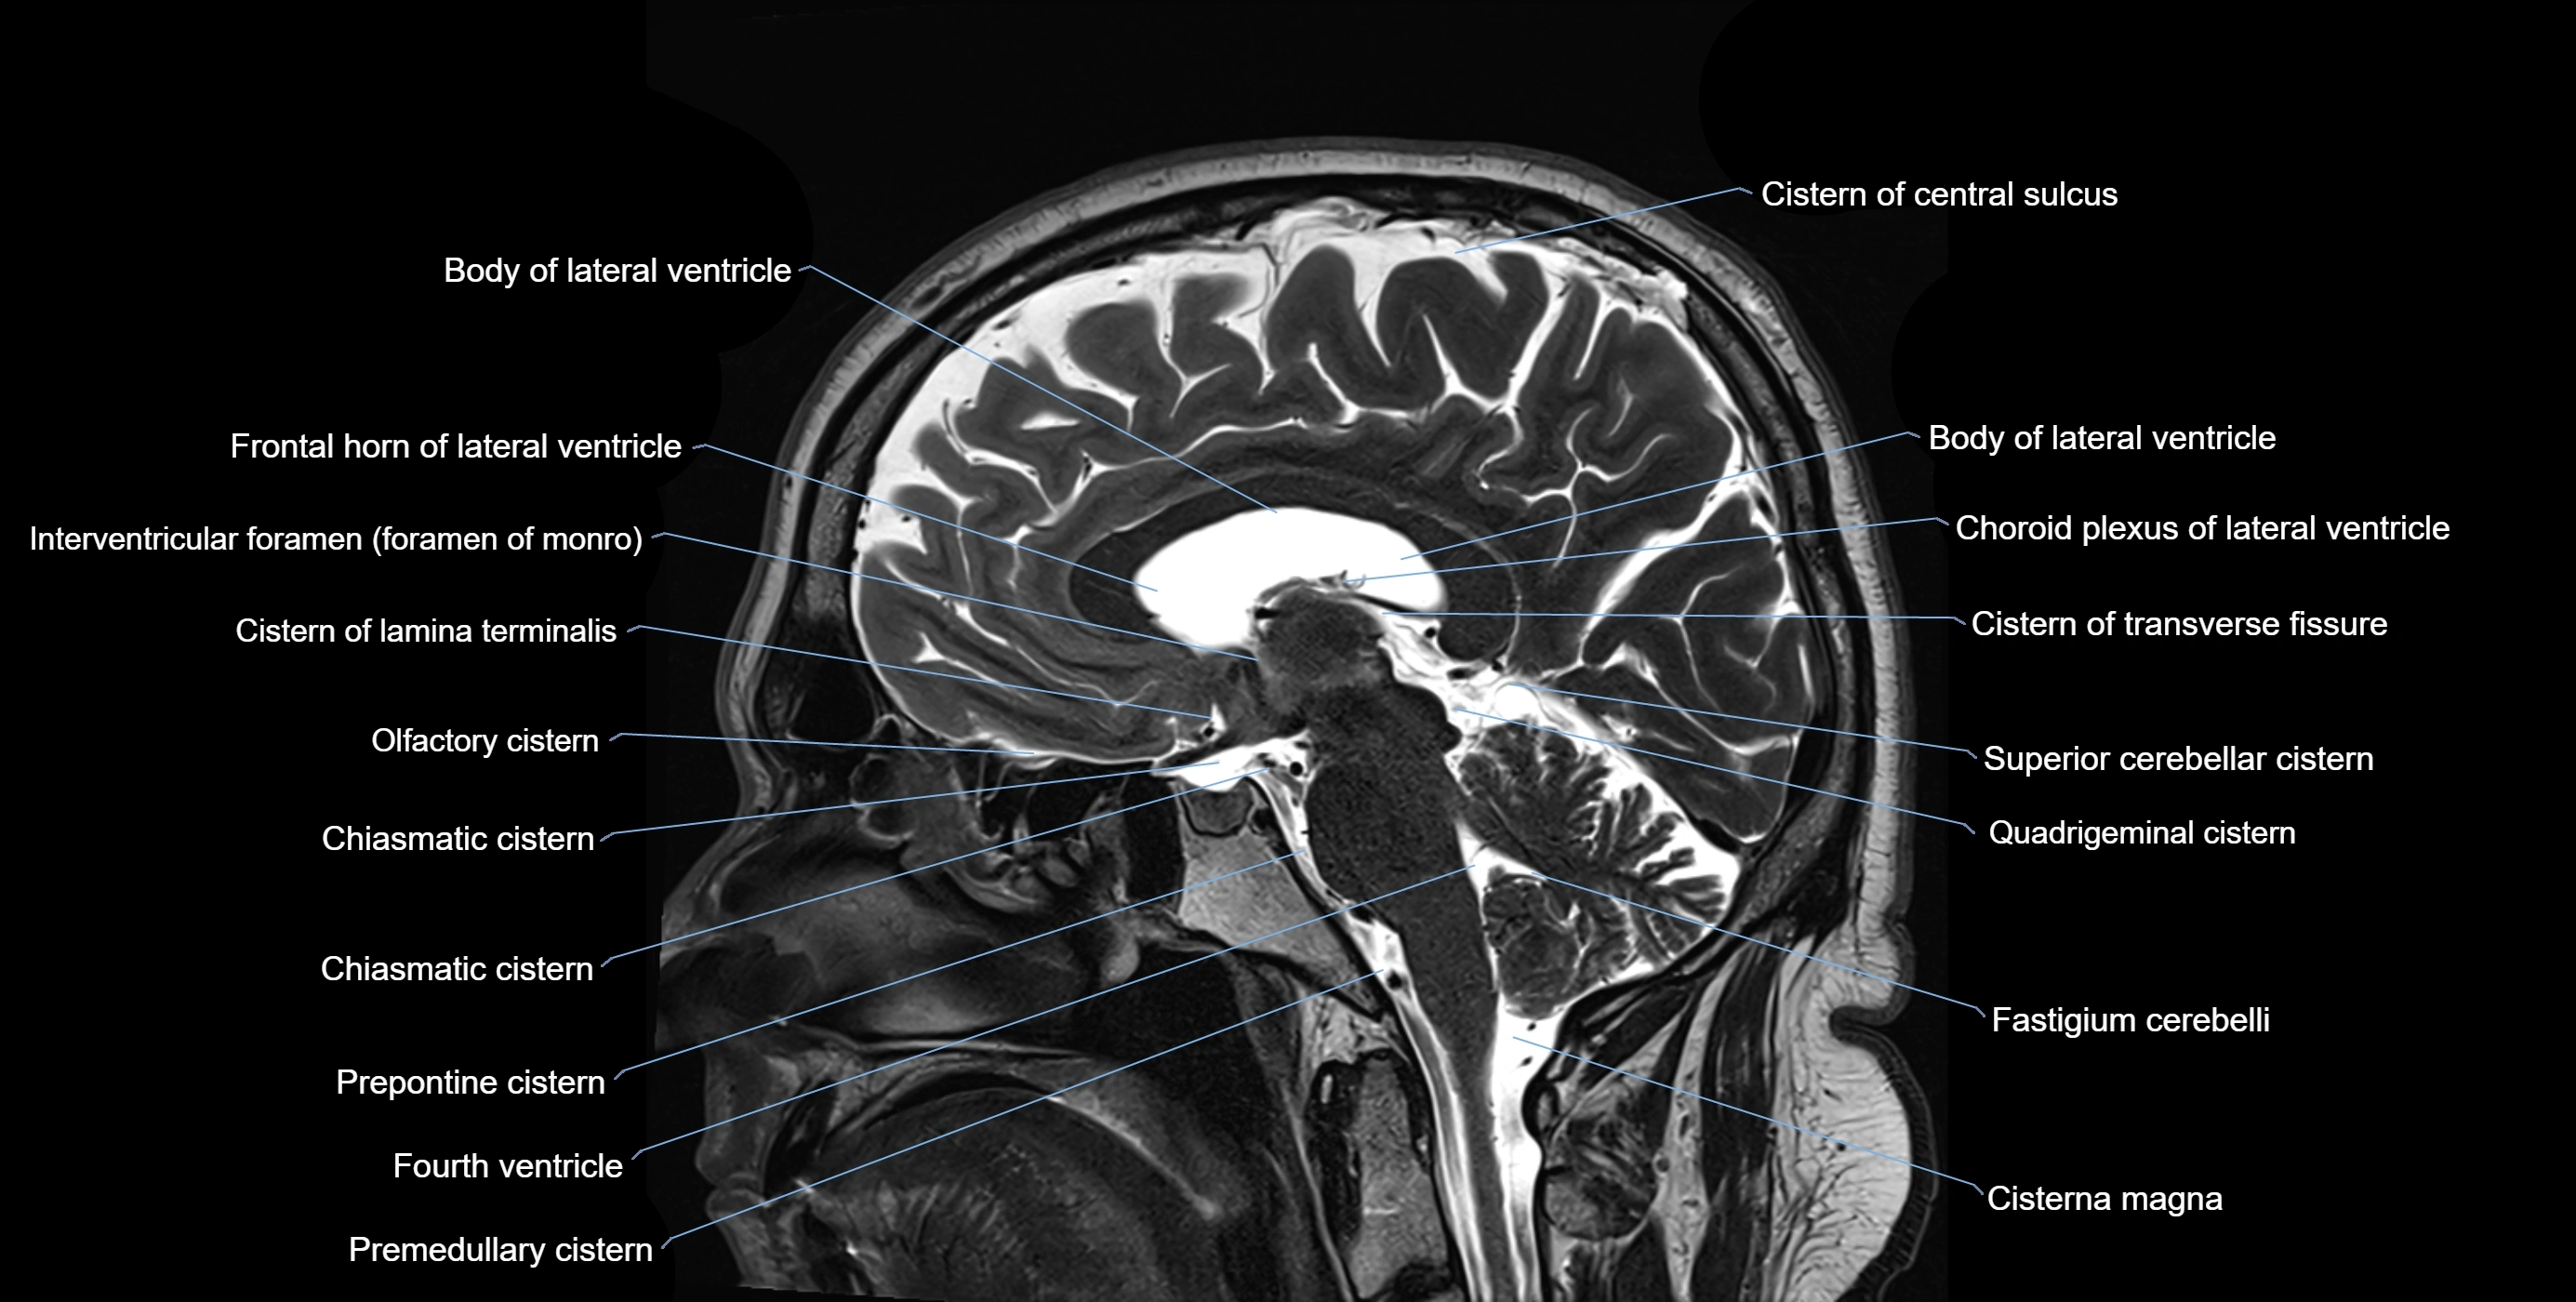

MRI images

image